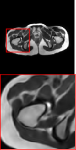

Figure 5 provides the qualitative comparison of the various methods on the four datasets at a scale of 4. The top, second, third, and bottom rows are the SR results under the FastMRI, clinical brain, clinical tumor and clinical pelvic datasets, respectively. The red boxes indicate the zoom-in region of complicated anatomical structures along with their corresponding error maps. Note that the brighter textures in the error maps, the lower the quality of the reconstructed images. As can be seen, compared to methods based on Transformers and CNNs, diffusion-based methods like DisC-Diff and DiffMSR (Ours) are capable of reconstructing high-realistic images with promising reconstruction metric scores (PSNR and SSIM). Nevertheless, while DisC-Diff can reconstruct high-precision MR images, it does not preserve the structure present in the original HR images, introducing some additional information that can affect medical diagnosis. In contrast, our method combines DM and PLWformer, which can preserve the original image’s structure while restoring high-frequency information.

In this section, we present more visual qualitative comparisons. Figures 8, 9, 10, and 11 show the reconstruction results of each method in FastMRI, clinical brain, clinical tumor, and clinical pelvic, respectively. As can be seen, although DisC-Diff can reconstruct MR images with high-frequency information, it fails to preserve the structure and content of the original Target HR image effectively, resulting in image distortion. In contrast, our proposed DiffMSR can restore high-frequency information while preserving the structure of the original HR image, indicating the effectiveness of the joint use of DM and PLWformer.